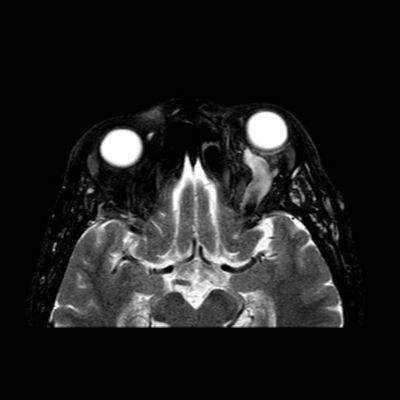

- A) Orbital MRG’de yağ baskılı T2A görüntülerde sol orbital globta ekzoftalmus (ok) izlenmiş olup retrobulbar yağlı dokuda kirlenmeler (ok) ve dilate superior oftalmik ven (ok) dikkati çekiyor. Beyin MRG’de kontrastlı T1A görüntüde sol kavernöz sinüste simetriğine oranla genişleme (ok) izleniyor.

- B) Pre ve post-kontrast yağ basklılı T1A görüntüler incelendiğinde superior oftalmik venin (oklar) kontrast madde verildikten sonra homojen dolum gösterdiği, dilate ve tortiyoze görünümde olduğu izleniyor.

- BT ve MRG: Propitozis, ekstraokuler kaslarda genişleme, superior oftalmik vende genişleme ve tortiyozite, ipsilateral kavernöz sinüste genişleme gösterilebilir. Serebral venöz konjesyonu olan ve intrakraniyal basınçları yükselen hastalarda serebral ödem, hemoraji, leptomeningeal ve kortikal venlerin dilastasyonunu görülebilir. Bunlara ek olarak travmaya sekonder olgularda BT ile eşlik eden fraktürler gösterilebilir.